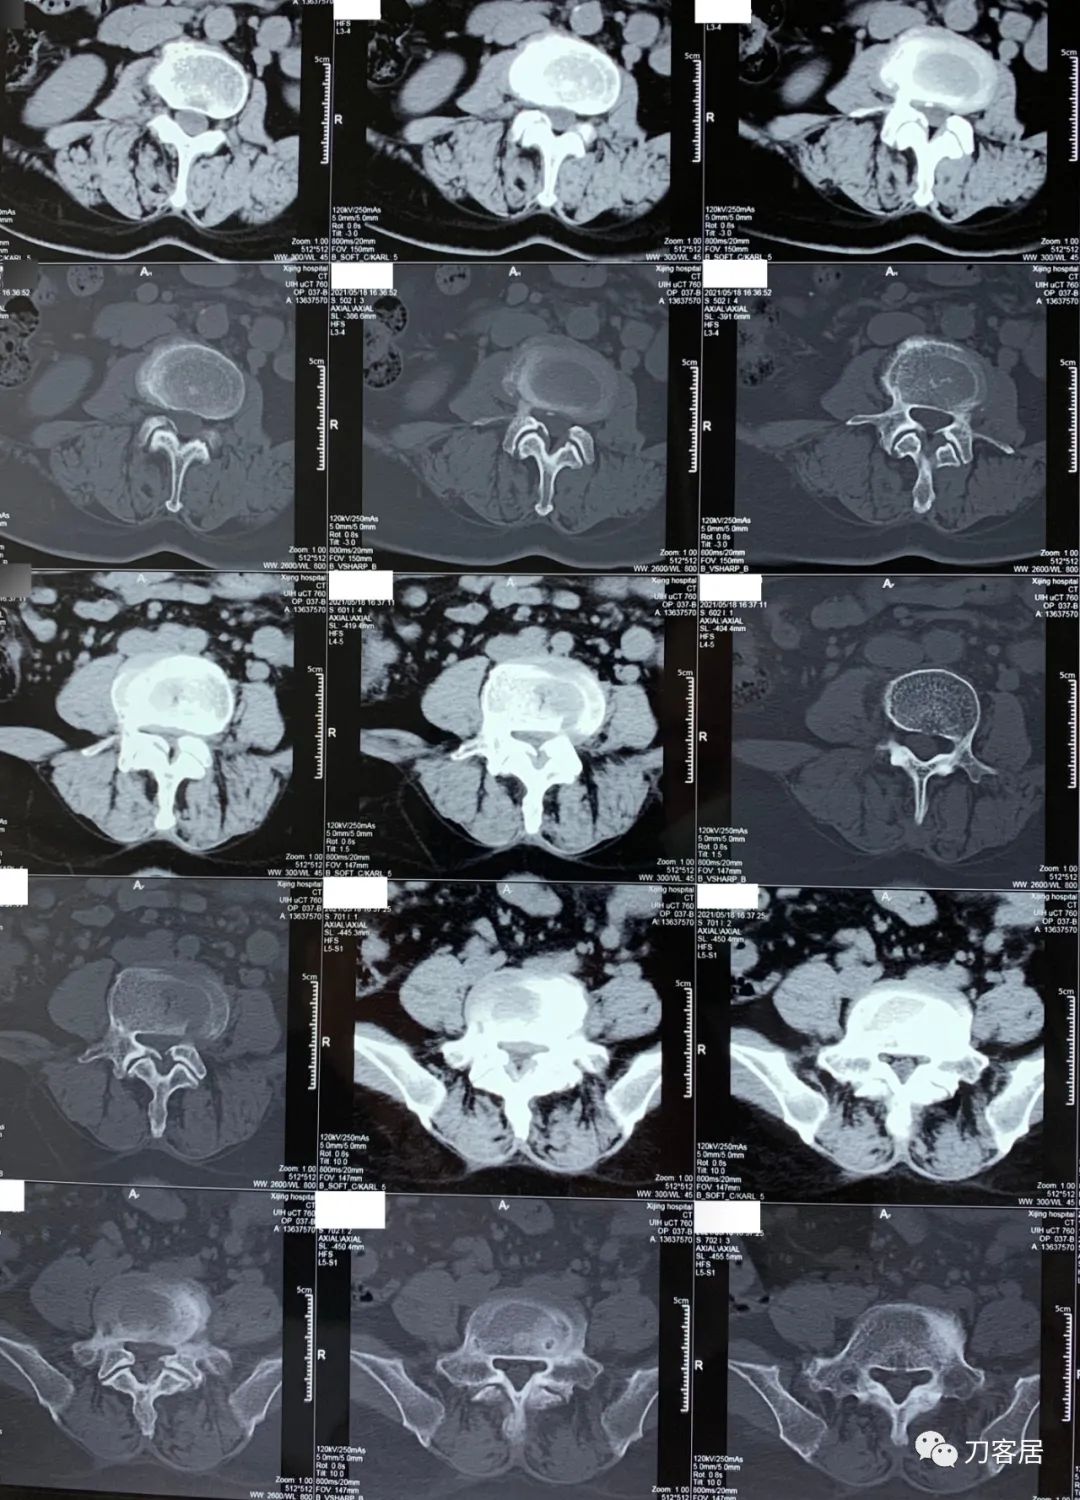

2021年5月17日,西京医院骨科门诊找我就诊,自带影像学检查资料提示腰椎侧弯,腰3-4,腰4-5椎间盘突出,黄韧带肥厚,椎管狭窄。

建议其查双光子骨密度,骨盆正位片以及腰椎间盘平扫。腰椎正侧位X线片以及动力位片,站立位脊柱全长正侧位X线片,以了解其是否有骨质疏松,并了解脊柱侧弯情况,腰椎局部X线表现情况和腰椎间盘突出和椎管狭窄情况。

从这个患者的影像资料分析,颈椎间盘突出问题不大,没有明确的上位神经元损伤表现,所以,不考虑颈椎和胸椎问题。腰椎侧弯畸形,但不严重。因为存在腰椎侧弯,使得腰椎MRI在扫描切面的时候,显示的椎间盘突出或椎管狭窄会有一定的误差,所以,又加做了经椎间盘的CT平扫,影像表现并不严重,综上,腰椎间盘突出,腰椎管狭窄,腰椎侧弯,不考虑手术治疗。同时,患者的主要痛苦是心理疾病,而不是器质性疾病,所以,以心身疾病治疗为主。虽然患者骨密度检查结果提示正常,但X线片显示骨质疏松,且其症状也与骨质疏松的症状有符合之处,比如静息痛,不能入睡,动作及姿势变换时痛加重等,所以,给予实验性抗骨质疏松治疗,以观疗效。